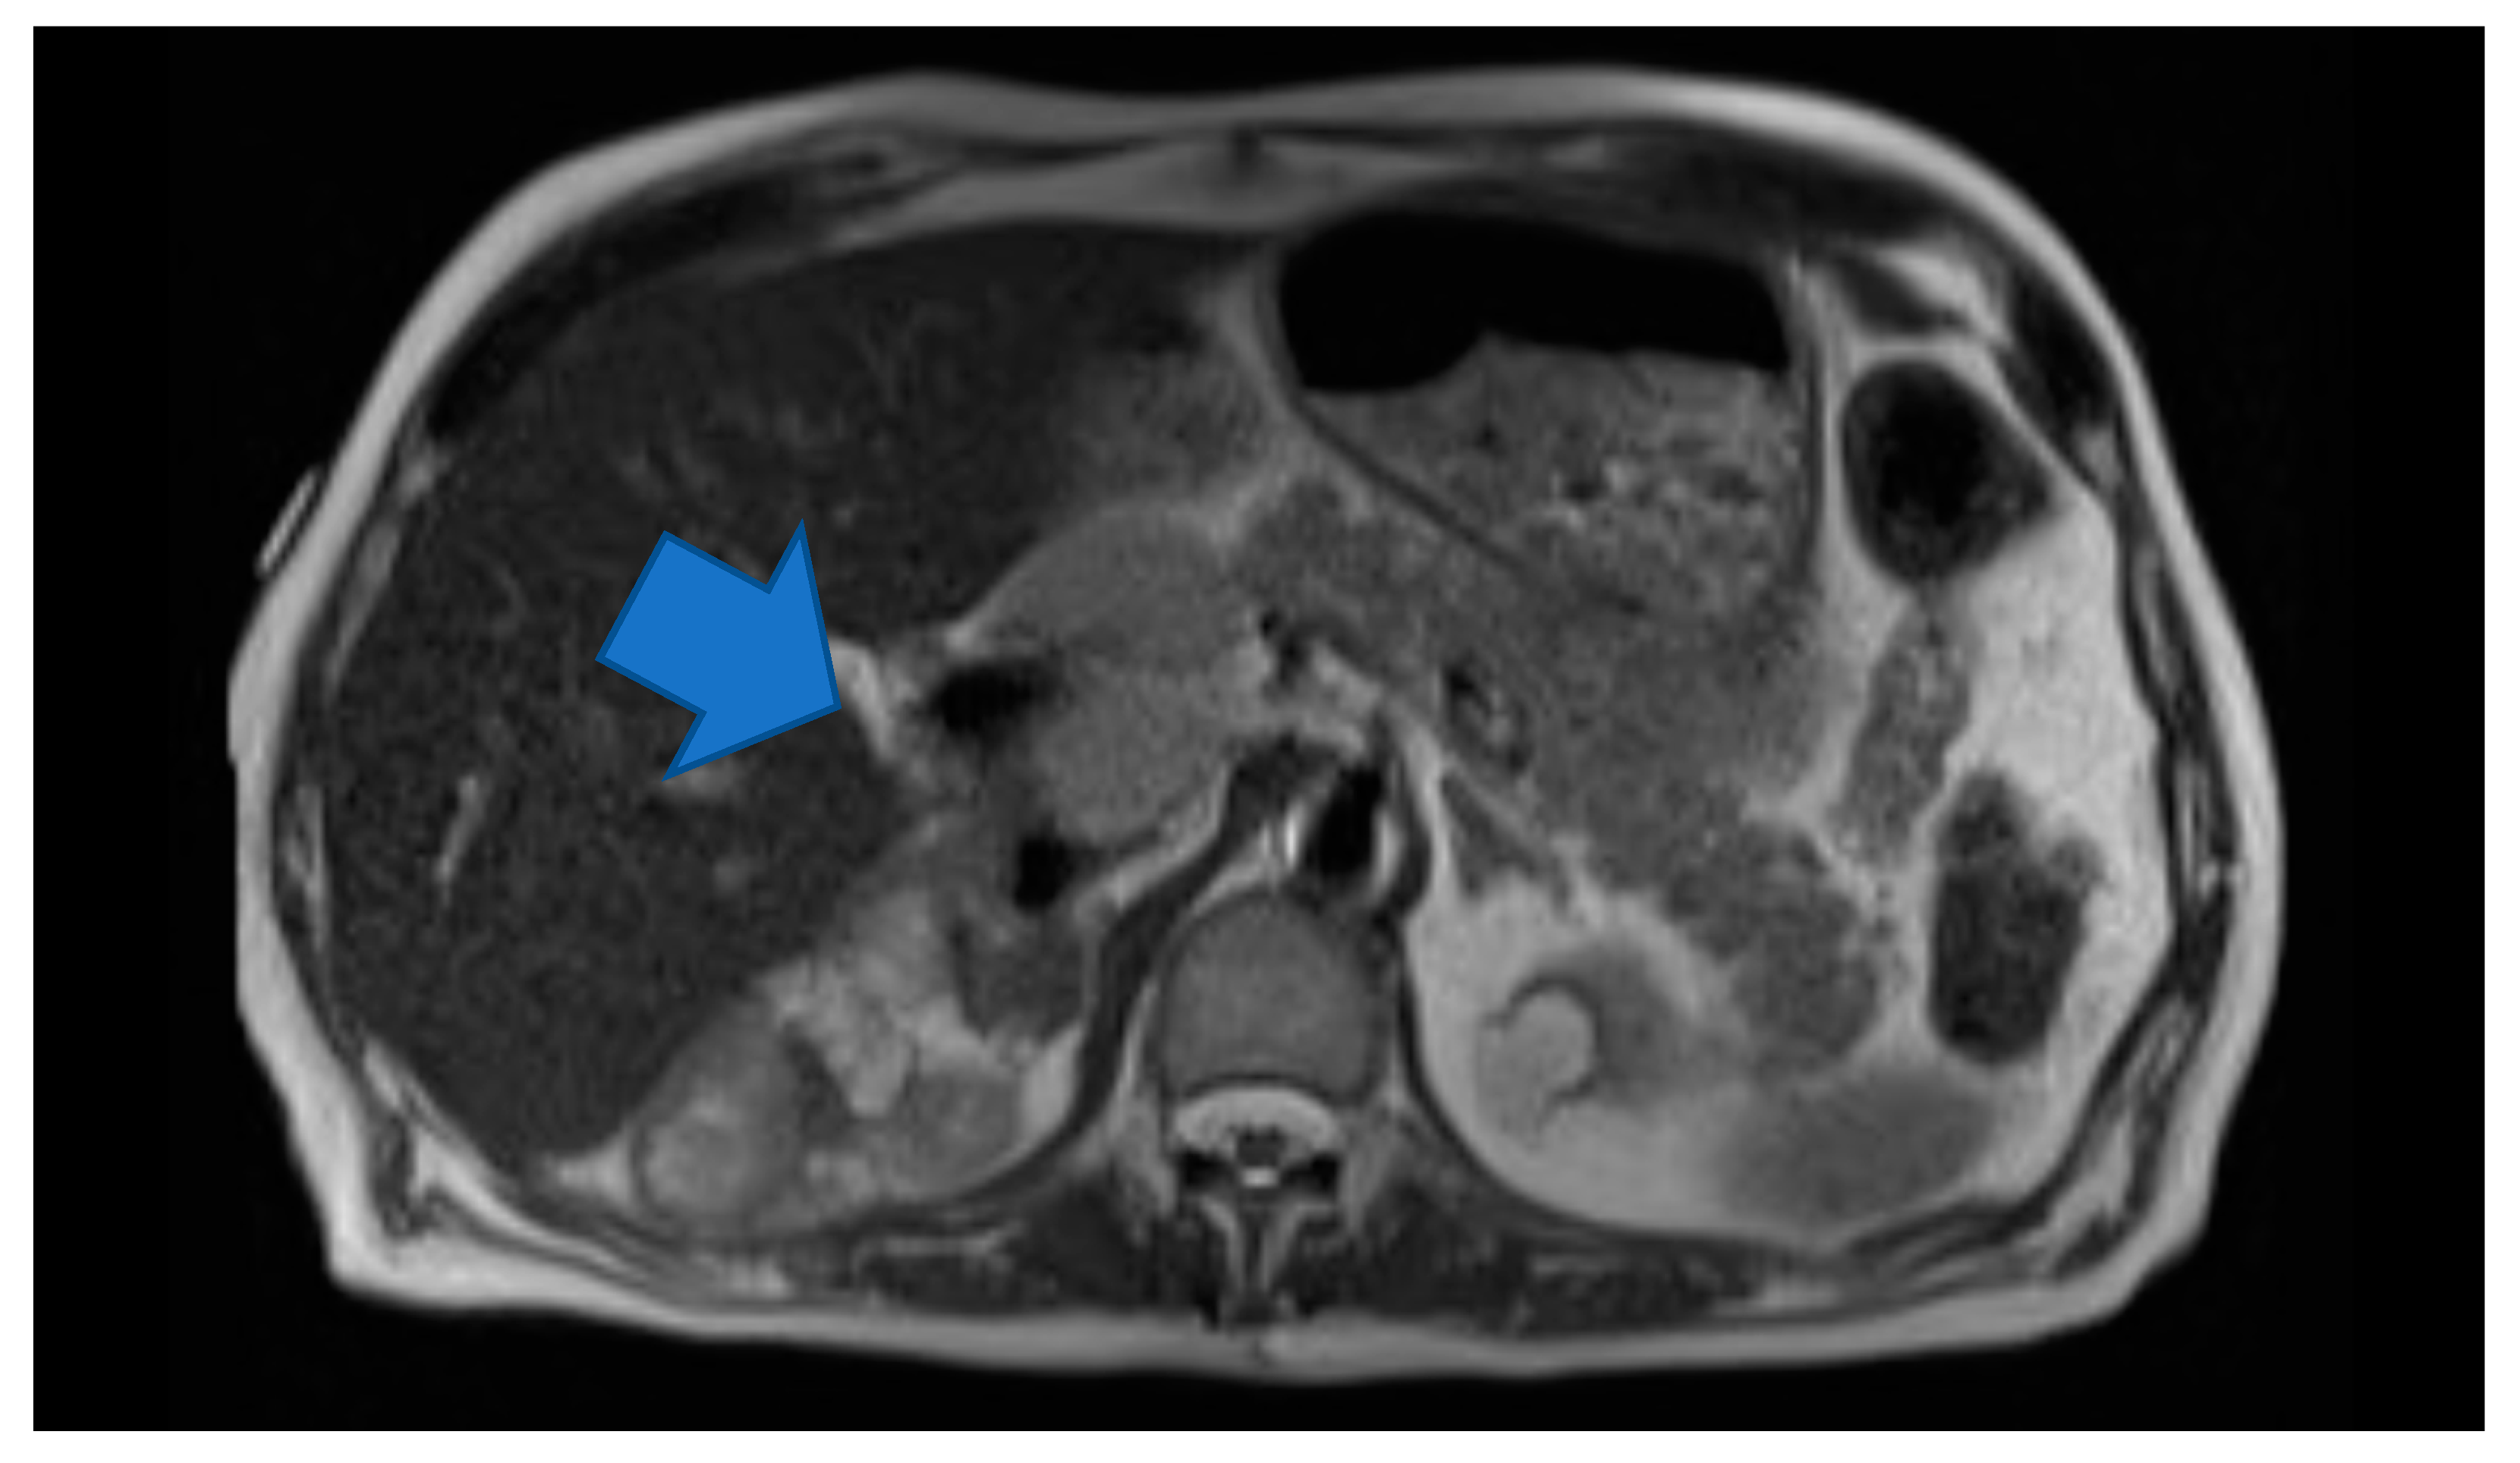

Laboratory testing revealed anemia (hemoglobin 9.2 g/dl) and hyponatremia (sodium 131). His urine metanephrine was 556 mcg/24 h, normetanephrine was 22,624 mcg/24 h and creatinine was 2.56 mg/dl. His INR was 4.26 which was high. On imaging, there was an abdominal mass on the right upper kidney as well as an abdominal hematoma. Computer tomography (CT) of abdomen showed left lower abdominal wall hematoma and prominent multilobulated soft tissue mass within the right retroperitoneum superior to the right kidney in the region of right adrenal gland involving the liver, vena cava and kidney. Magnetic resonance imaging (MRI) of abdomen and pelvis showed postoperative changes after right adrenalectomy with 7.8 cm heterogenous multilocular enhancing mass in the surgical bed abutting the right posterior wall and close to the right kidney and Inferior vena cava (IVC). The mass and the enlarged regional lymph nodes together caused marked compression of the IVC. Heterogeneity and enhancing focus in the posterior right hepatic lobe indicated the invasion of the right adrenal gland. (Figure 1) Positron emission tomography (PET) gallium-68 DOTA-DPhe1, Tyr3-octreotate ((68Ga)Ga-DOTA-TATE) imaging showed liver and mesentery metastases. (Figure 2) He was diagnosed with right metastatic malignant adrenal lesion surrounding IVC along with the syndrome of inappropriate antidiuretic hormone (SIADH).

Figure 1. Axial HASTE. Large multilocular heterogeneous mass in the right adrenalectomy bed and large regional lymph nodes causing Inferior vena cava (IVC) compression.